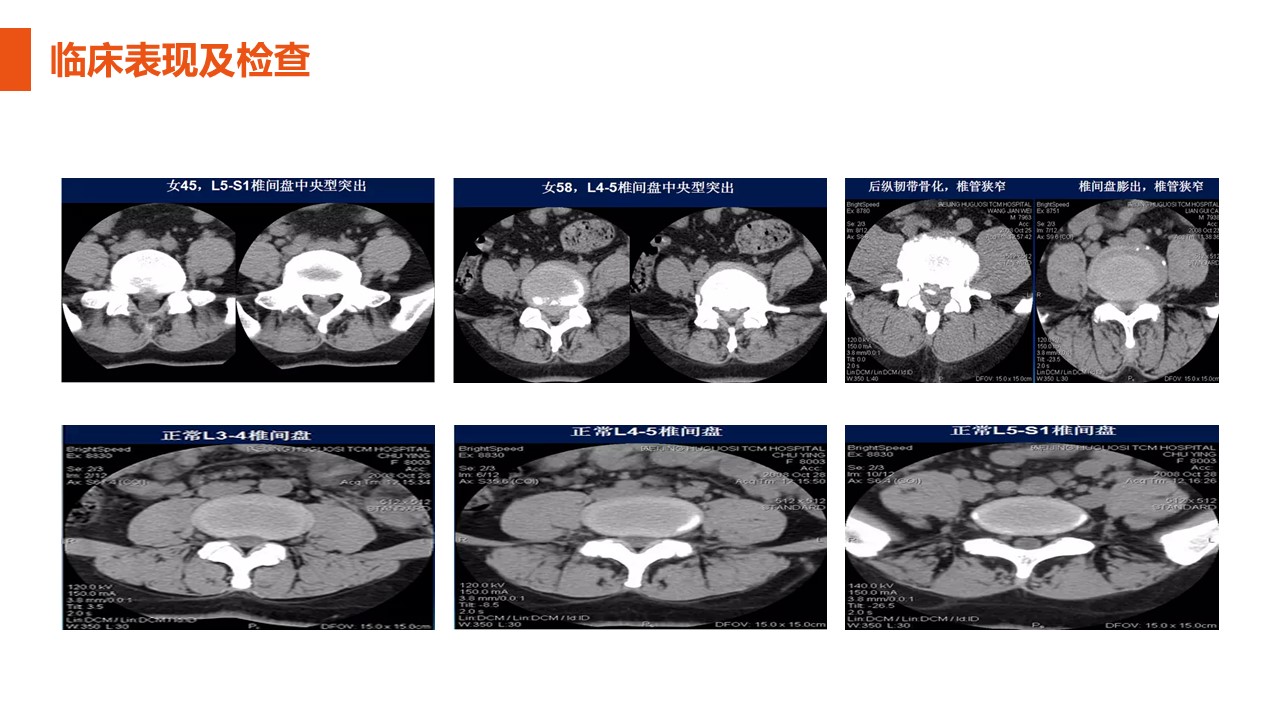

腰椎间盘突出症1